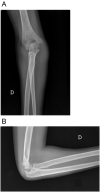

Case presentation: A 7-year-old girl presented to the emergency department after a fell on his right elbow while playful activity at home. The elbow X-ray showed acute trans-olecranon fracture dislocation of the elbow associated with a radial head fracture. A pre-operative 3D TC scans confirmed and clarified the injury pattern. However, stress radiographs performed in the operating room under anesthesia revealed an associated severe valgus instability caused by medial collateral ligament disruption. The olecranon fracture was fixed with two crossing 1.5 mm K-wires and the angulated radial neck fracture was fixed with a retrograde 1.5 mm K-wire by S.E.R.I. technique.